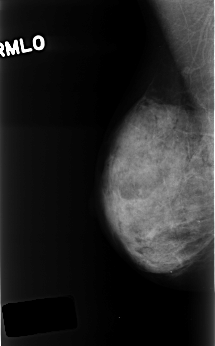

C_0400_1.RIGHT_MLO

RIGHT_MLO LINES 4488 PIXELS_PER_LINE 2792 BITS_PER_PIXEL 12 RESOLUTION 50 NON_OVERLAY